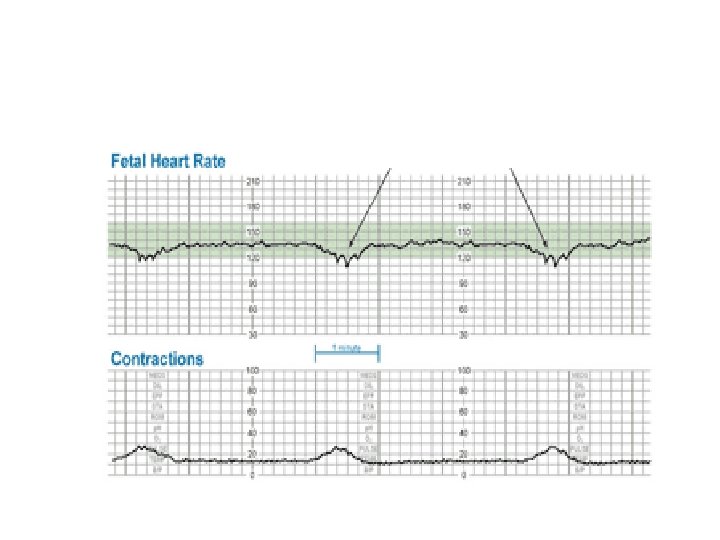

Decelerations The type of the deceleration is distinguished on the basis of its waveform : · Abrupt (variables) decrease in FHR below baseline with onset to nadir < 30 seconds. · Gradual decrease and return to baseline with time from onset of the deceleration to nadir >30 seconds.

Variable Deceleration Abrupt decrease in FHR of > 15 beats per minute measured from the most recently determined baseline rate. The onset of deceleration to nadir is less than 30 seconds. The deceleration lasts > 15 seconds and less than 2 minutes. A shoulder, if present, is not included as part of the deceleration. Variable decelerations may be observed in up to 50% of NSTs. If nonrecurrent and <30 seconds, they are of no clinical significance.

Variable Deceleration Typical: • shoulders Atypical : • Overshoot • Loss of primary shoulder • Slow return to baseline (late component) • Baseline returns to a lower level(after deceleration) • Biphasic(W shape) • loss of variability during deceleration

Prolonged Decelerations A decrease in FHR of > 15 beats per minute measured from the most recently determined baseline rate. The deceleration lasts >= 2 minutes but less than 10 minutes. Causes: • Maternal hypotension • Rapid descent of fetal head • Uterine hyperactivity • Abruption • Cord prolapse • Artifact (maternal heart rate) • Cord compression* • Maternal seizure